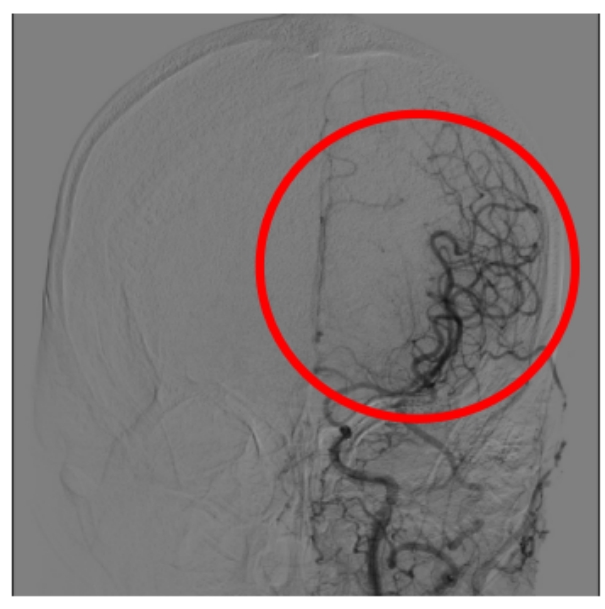

图8颈内动脉末端及分支血流恢复